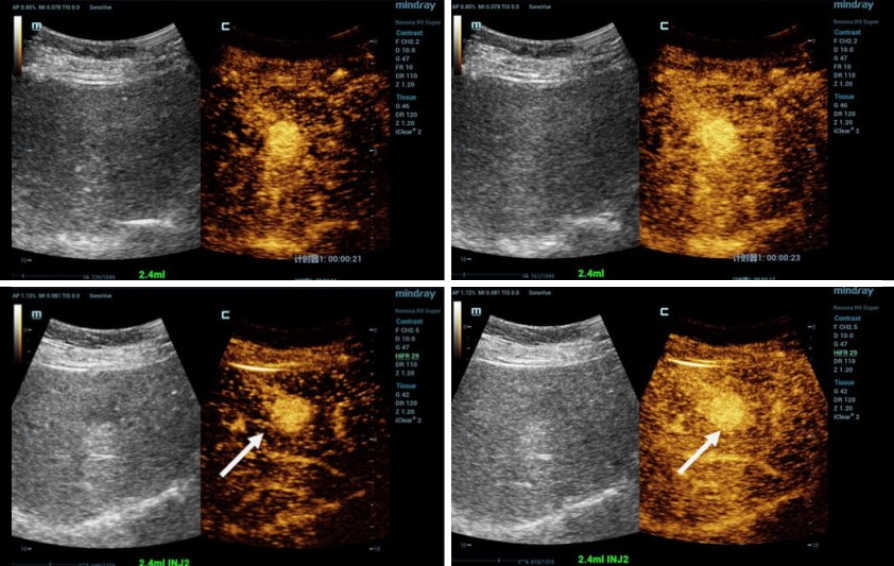

Ultrasonografi kontras (CEUS) adalah bidang yang sangat dinamis dan dalam beberapa tahun terakhir inovasi teknologi telah semakin meningkatkan kualitas gambar. Salah satu inovasi ini adalah ultrasonografi kontras tingkat frame tinggi (HiFR CEUS) yang dapat menghasilkan hingga sepuluh kali lebih banyak gambar dibandingkan ultrasonografi konvensional ŌĆō dalam waktu yang sama. Peneliti di tujuh pusat di Jerman, Swiss, dan Tiongkok sedang mengevaluasi efektivitas HiFR CEUS dalam mendiagnosis lesi hati kecil. Profesor Dr Yi Dong dari Departemen Ultrasonografi, Rumah Sakit Xinhua, Shanghai Jiaotong University School of Medicine, dan Profesor Dr Christoph F Dietrich, Departemen Penyakit Dalam Umum, Hirslanden Bern, Swiss, menjelaskan latar belakang dan tujuan dari studi ini.

Yi Dong: 'Tujuan utamanya adalah diagnosis yang lebih presisi dari lesi hati fokal dengan diameter kurang dari 3 cm pada pasien dengan dan tanpa sirosis hati. Studi sebelumnya telah menunjukkan bahwa HiFR CEUS memvisualisasikan pola dan morfologi pembuluh darah pada lesi tersebut dengan sangat baik. Kami mengharapkan HiFR CEUS dapat menawarkan resolusi temporal dan spasial yang lebih baik, dengan kata lain gambar berkualitas lebih tinggi dari lesi hati yang sangat kecil. Ini akan meningkatkan kepercayaan dalam karakterisasi dan diagnosis lesi ini. Penelitian sebelumnya tentang karsinoma hepatoseluler (HCC) telah menemukan bahwa ada perbedaan yang cukup signifikan apakah lesi kecil tersebut terletak pada latar belakang hati sirotik atau pada hati yang sehat.'

Yi Dong: 'Dalam sistem ultrasonografi konvensional, tingkat frame dalam pencitraan kontras non-jantung adalah sekitar sepuluh frame per detik. Sistem HiFR CEUS yang kami gunakan, Mindray Resona 9, jauh lebih cepat: dapat menghasilkan hingga 100 gambar per detik. Tingkat frame yang tinggi seperti ini menawarkan visualisasi yang lebih baik dari morfologi vaskular dan menunjukkan detail perfusi mikrovaskular serta pelacakan gerakan yang lebih baik. Singkatnya: ini meningkatkan efisiensi diagnostik CEUS. Dalam studi kami, kami akan fokus pada arsitektur vaskular selama fase arterial CEUS, fase wash-in awal, waktu peningkatan kontras, eliminasi, dan pola yang relevan.'

Christoph Dietrich: 'Sekitar 70% dari total aliran darah hati melalui vena porta yang membawa nutrisi dan produk metabolik dari saluran pencernaan serta racun untuk detoksifikasi ke hati. Darah arterial juga menyediakan 30% oksigen. Ultrasonografi hati kontras dengan demikian menggunakan fase arterial serta fase vena porta untuk menghasilkan gambar. Dalam hati sirotik, vena porta rusak dan darah tidak lagi dapat didetoksifikasi. Jadi, terkait pencitraan, fase vena porta menawarkan informasi yang lebih sedikit. Oleh karena itu, studi kami akan fokus pada fase arterial. Karena tingkat frame yang tinggi, volume data relevan yang tinggi diperoleh meskipun fase vena porta diabaikan. Ini seperti jaring ikan: semakin rapat tenunan jaringnya, semakin banyak ikan yang bisa Anda tangkap. Terkait pencitraan: semakin tinggi kepadatan garis, semakin tinggi resolusinya. Lebih banyak tumor tertangkap dan dapat ditangani sesuai dengan pedoman medis saat ini.'